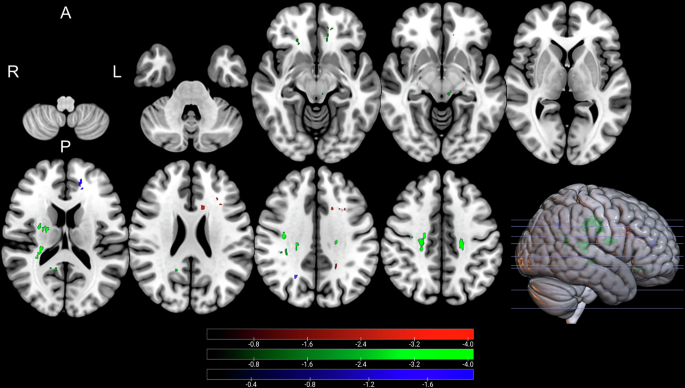

Whole brain analysis of NODDI parameters indicated that both ODI and NDI were significantly correlated with changes in postoperative UPDRS part III scores. These findings are illustrated in Supplementary Tables 2 and 3 as well as Figs. 2 and 3 (ODI) and Supplementary Figs. 3 and 4 (NDI values). Higher ODI values in the left pallidum, bilateral putamen, and bilateral insular cortex were associated with greater change in postoperative motor symptoms (P1-6, CWP: <0.001–0.038, Fig. 2). Conversely, negative associations were exclusively observed in white matter regions adjacent to the left middle frontal gyrus, left cingulate gyrus, and left precuneus (N1-3, CWP: <0.001-0.019, Fig. 3). Furthermore, higher ODI and NDI values in the bilateral insular cortex were related to a greater reduction in postoperative motor symptoms (ODI: P3, P5, CWP: <0.001-.003; NDI: P1–P3, CWP: <0.001–0.032). Additionally, increased NDI values in the left putamen were liked to greater reduction in postoperative motor symptoms (P1, CWP: <0.001). Negative associations between NDI and postoperative motor symptoms were identified in white matter regions adjacent to the left middle frontal gyrus, left precentral gyrus, right precuneus, and left paracingulate gyrus, corresponding to the previously mentioned negative ODI-clusters (N1-3, CWP: <0.001−0.019).

Clusters with a negative association between PD patients’ ODI-values and postoperative change in UPDRS (red), time spent in ON (green), and time spent in OFF (blue), as revealed by the whole brain analysis. P-values were corrected for multiple comparisons using a permutation-based approach. Clusterwise P-Values were corrected for multiple comparisons using a permutation-based approach and shown as the negative decadic logarithm of the p-value.